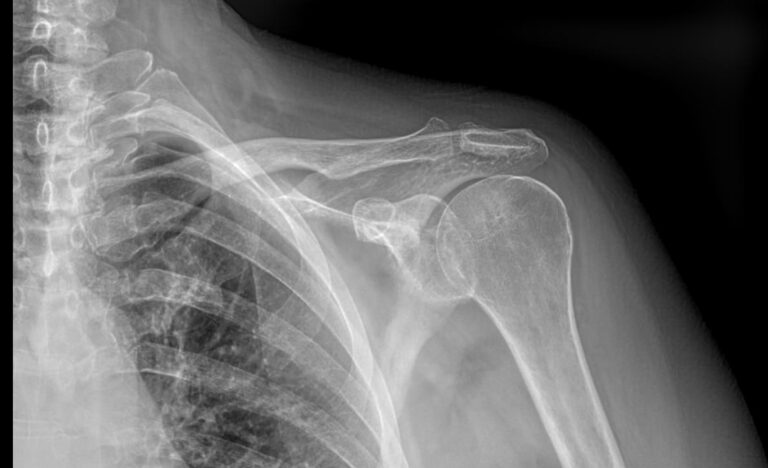

На снимке видны:

• Рукоятка грудины ― ее верхняя часть;

• Грудинные концы ключиц ― в норме или перелом;

• Суставные щели между грудиной и ключицами, их состояние, говорящее о хронических воспалениях;

• Соответствие суставных поверхностей ― норма, подвывих, вывих;

• Новообразования.